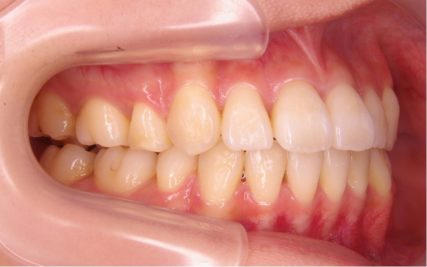

でこぼこ/20代女性

- 不正咬合/叢生(でこぼこ)

- 治療前

- 上下とも前歯のスペース不足が認められた。歯のサイズと顎の幅とのバランスが不調和な事が原因の1つとして考えられる。

- 治療後

- 前歯部のでこぼこが解消され、正常咬合を獲得する事が出来た。又、歯科矯正用アンカースクリューを用いる事で抜歯スペースを有効に利用できた。